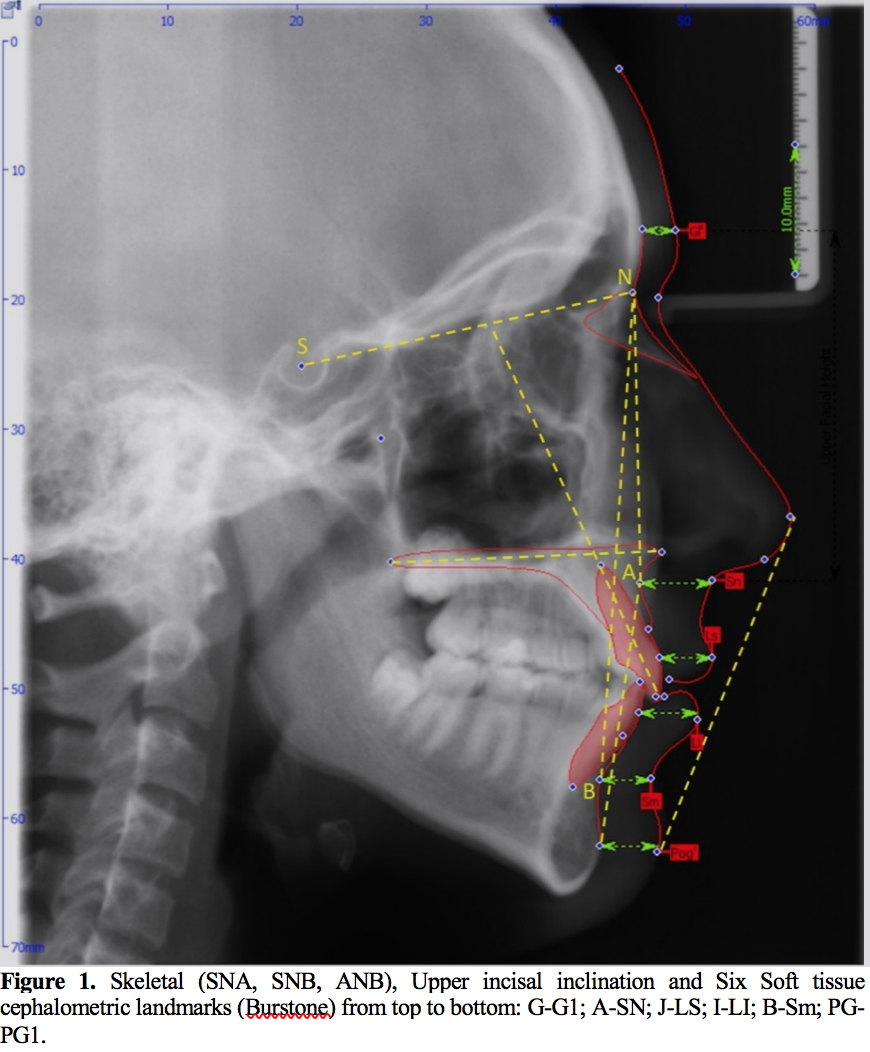

Methods: 221 lateral cephalometric radiographs of patients aged between 16–26 years (male [n=114] and female [n=107]) belonging to central and eastern regions of Saudi Arabia was taken from Orthodontic clinics database among Riyadh and eastern regions, Saudi Arabia. OnyxCeph3TM (Image Instruments GmbH Olbernhauer Str. 5 D 09125 Chemnitz Germany) digital software was used to analyze the dentoskeletal classification of the sample as Class I (n=84), Class II Division 1 (n=42), Class II Division 2 (n=33), Class III (n=62). Burstone analysis of six linear measurements for facial soft tissue thickness (FSTT) was used. All statistical analyses were set at a significant level of when (P<0.05).

Methods: 221 lateral cephalometric radiographs of patients aged between 16–26 years (male [n=114] and female [n=107]) belonging to central and eastern regions of Saudi Arabia was taken from Orthodontic clinics database among Riyadh and eastern regions, Saudi Arabia. OnyxCeph3TM (Image Instruments GmbH Olbernhauer Str. 5 D 09125 Chemnitz Germany) digital software was used to analyze the dentoskeletal classification of the sample as Class I (n=84), Class II Division 1 (n=42), Class II Division 2 (n=33), Class III (n=62). Burstone analysis of six linear measurements for facial soft tissue thickness (FSTT) was used. All statistical analyses were set at a significant level of when (P<0.05).